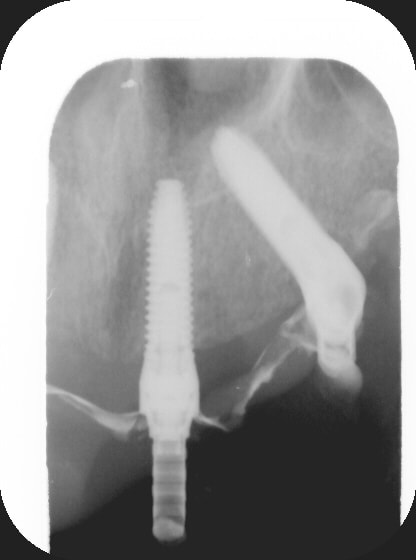

des news....nous venons de finir il y a 1h l' arcade antagoniste (mandibulaire s'il y en a qui ne suivent pas ;) en all on 4 version nobel guide... 4 implants de 4x18mm tous bloqués à plus de 45 newton...si vous etes sages, je vous poste quelques photos ;)

PS: on a fait du nobel guide à ciel ouvert....

je vous montre le bas ;) oups!

(rrrhhh....les radio, dans ces secteurs là aplatissent tout, on dirait des implants presque parallèles... rrhhhh...)

Gin1 vfjd6v - Eugenol

Gin2 lzgl9h - Eugenol

Gin3 zmirus - Eugenol